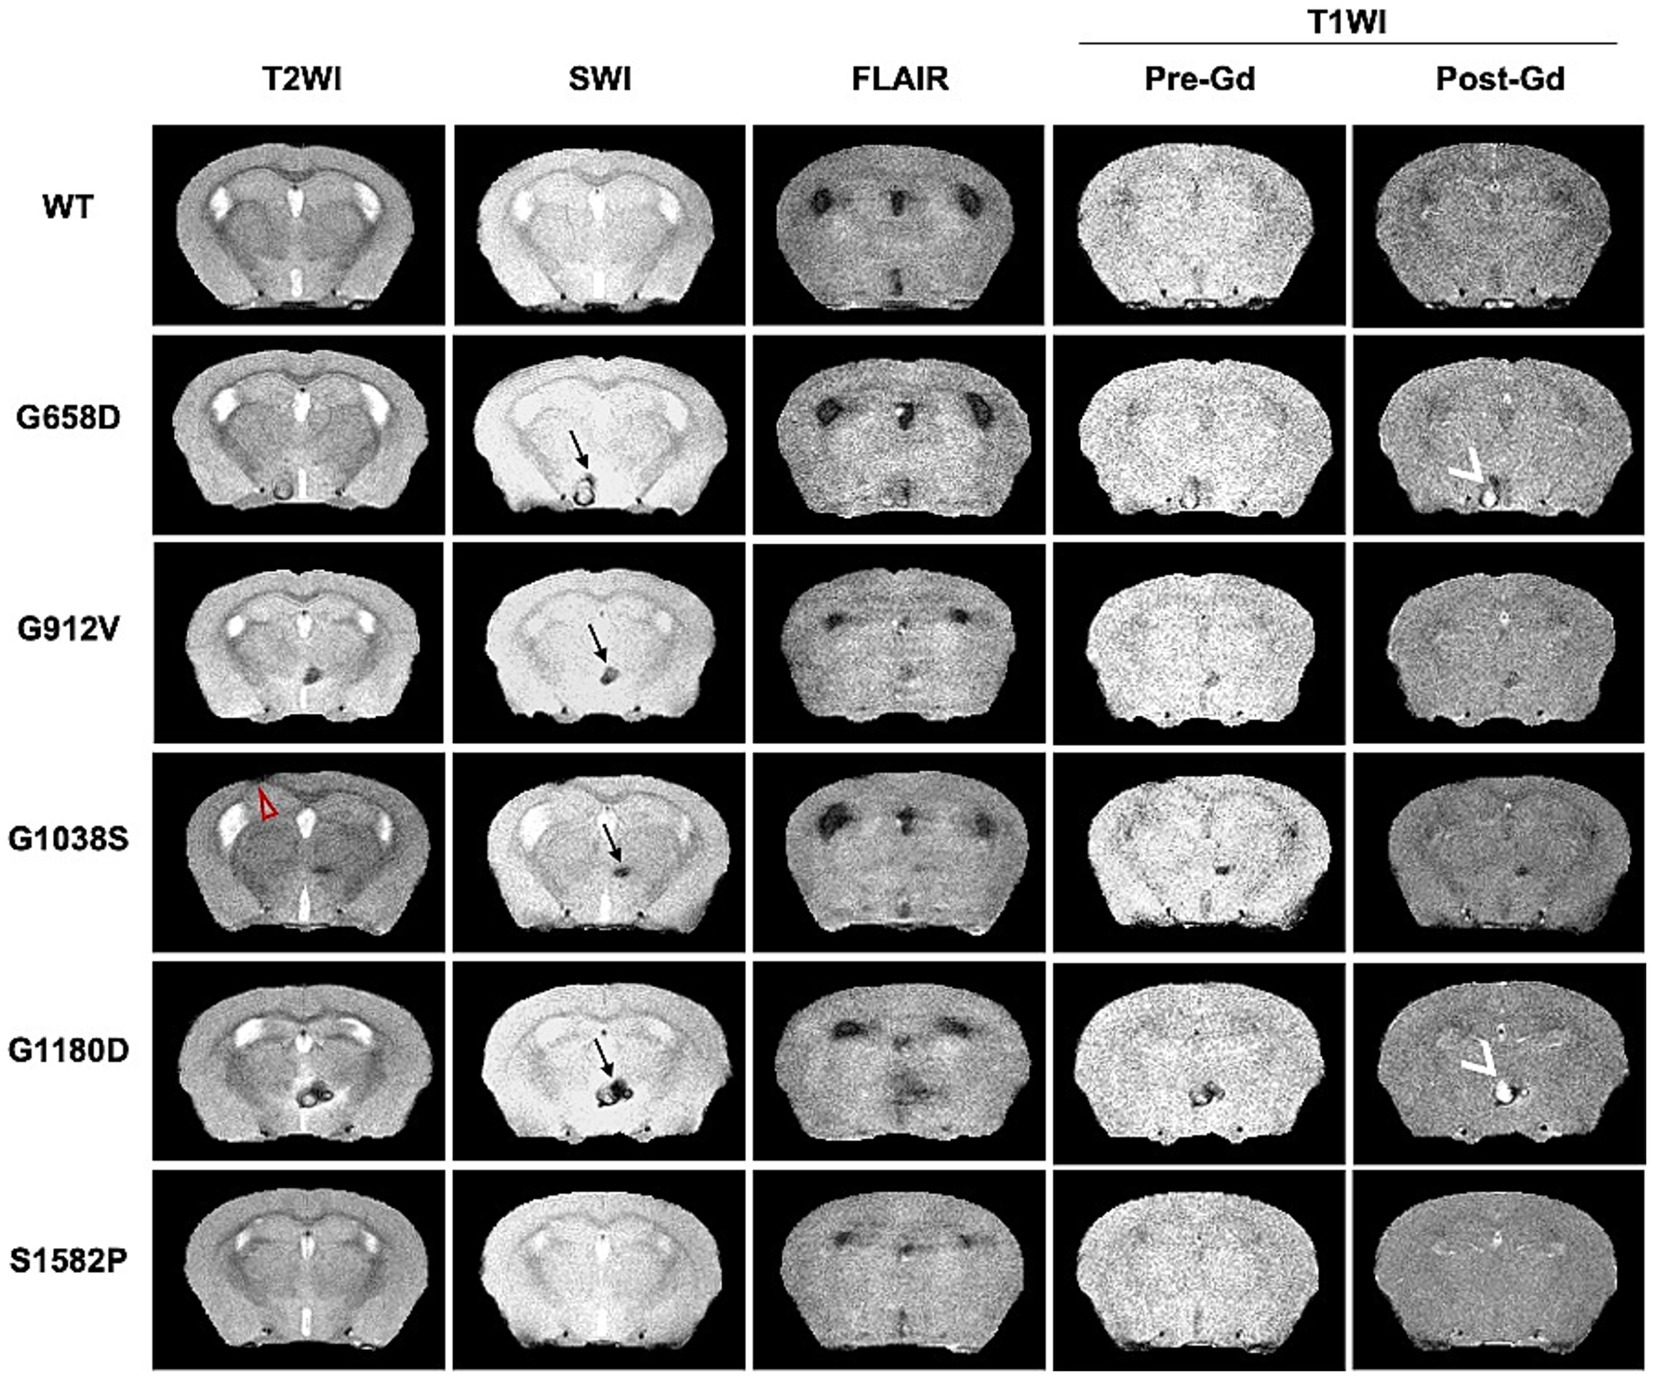

Representative brain images after skull-stripping are also shown for all five genotypes and all five MRI modalities used in this study (Figure 3) to demonstrate the phenotypic variability of radiological manifestations among Col4a1 mutant mice. Of note, one mouse from one strain (Col4a1+/G1038S) presented SWI sensitive lesions along with schizencephaly (red arrow in Figure 3), a radiological features associated with Gould syndrome (Yoneda, 2013; Matsumoto, 2015; Smigiel, 2016; Khalid, 2018). In three out of five genotypes (Col4a1+/G658D, Col4a1+/G1180D, and Col4a1+/G1038S), T1WI showed gadolinium (Gd) enhanced lesions. These results indicate that Col4a1 mutations can lead to both macro- and micro-scopic structural changes detectable by MRI.

Figure 3

Representative multimodal MRI of Col4a1 mutant and wild-type mice acquired at 14.1 Tesla. Representative images of all five different MRI modalities are shown for all five genotypes (after skull-striping via U-net). SWI-positive lesions (black →) were detected in all Col4a1 mutant strains, but not in WT mice. Increased post-Gd enhancement (white >) was only found in Col4a1+/G658D (G658D), Col4a1+/G1038S (G1038S), and Col4a1+/G1180D (G1180D) by T1WI. One schizencephaly case was found in Col4a1+/G1038S mice and indicated by red ▻ in T2WI.